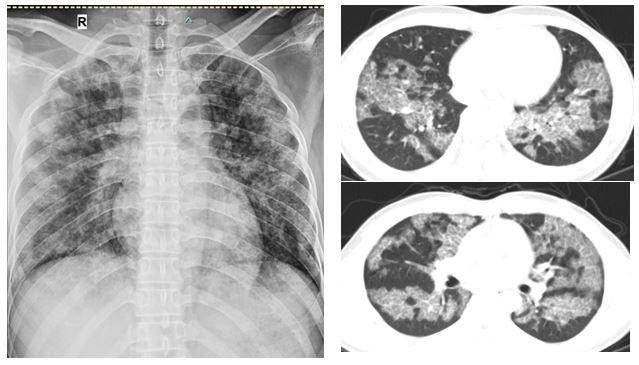

| Người bệnh được chụp cắt lớp vi tính ngực cho thấy tổn thương lan tỏa hai phổi, đây chính là nguyên nhân gây khó thở |

Dựa trên các dữ liệu lâm sàng, xét nghiệm dịch phế quản và phim chụp cắt lớp vi tính ngực, người bệnh được chẩn đoán "Bệnh tích protein phế nang" và được chỉ định rửa phổi.